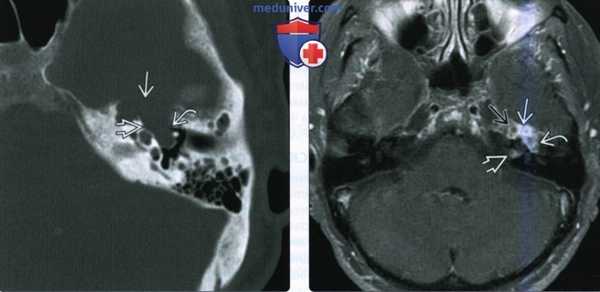

При СКТ головного мозга в костном режиме выявлен расширенный канал подъязычного нерва с деструкцией его стенок. Заднелатеральная стенка практически отсутствовала, вследствие чего полость канала сообщалась с просветом яремного отверстия (рис. 2). Рис. 2. СКТ головного мозга пациентки В. в костном режиме до операции. Определяется деструкция канала подъязычного нерва справа, канал отделен от полости яремного отверстия тонкой костной перегородкой (указано стрелкой).

(Слева) При МРТ Т1 в аксиальной проекции наблюдается асимметрия сигнала языка. Правая половина языка не изменена; четко отграниченная левая половина языка дает патологически усиленный сигнал. Усиление сигнала свидетельствует о жировой инфильтрации и требует исследования канала подъязычного нерва.

(Справа) При МРТ Т1 с КУ в аксиальной проекции определяется дольчатое объемное образование левого подъязычного канала, распространяющееся в цистерну продолговатого мозга. Обратите внимание на отсутствие изменений правого канала подъязычного нерва. Отмечается равномерное контрастирование объемного образования, что характерно для шванномы. В ткани крупных опухолей часто наблюдаются кистозные изменения.